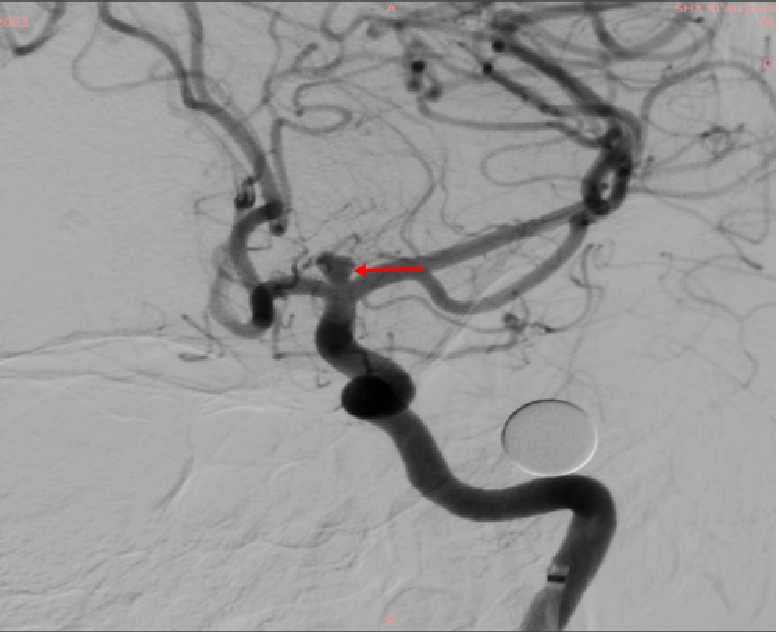

此次为一中年女性患者,以“头晕、头痛半月”之主诉来我院神经内科就诊,在完善了脑血管造影后,发现了该患者左侧大脑中动脉及大脑前动脉的分叉处有一大小约4.17×3.76mm大小的动脉瘤。由于该动脉瘤位置正对血流冲击位置,且有子囊形成,血压波动或者情绪波动等诱因都可能引发动脉瘤破裂出血,一旦出血可能危及生命。患者及家属十分忧虑,听闻我院神经外科脑血管亚专业组在脑动脉瘤的治疗方面有着丰富经验,遂转往我科继续治疗。

许刚副主任在仔细研究过患者的病历及影像资料后,建议患者早期行手术治疗,给出了患者三个治疗方案,开颅夹闭手术,常规弹簧圈加支架介入栓塞手术,而最后一种,则是目前最先进的方式WEB™植入术。经过详细告知和沟通,患者家属最终选择了行WEB™植入手术。于是在充分完善术前准备后,在影像介入室、麻醉科以及屈满莉护师的全力配合下,许刚副主任、张明副主任医师在全麻下为患者施行了大脑中动脉瘤内扰流装置WEB植入术,因为有之前的手术经验,手术过程十分顺利,仅用时15分钟就完成了WEB植入,术中即刻造影显示动脉瘤内造影剂滞留明显,其余左侧大脑中动脉、大脑前动脉等血管均通畅。患者术后顺利苏醒,拔管后未诉特殊不适,言语功能及肢体功能均未受影响。2天后患者出院。

术前动脉瘤影像